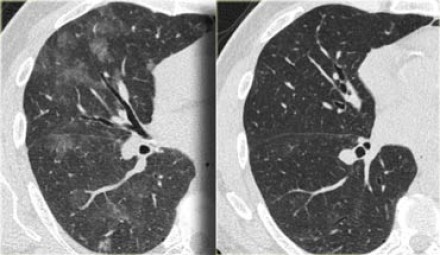

UIP Pattern–

Stacked cystic spaces/honeycombing, lower lobe predominant, subpleural reticulation, architectural distortion, and volume loss

Ground glass opacities + fibrosis, lower lobe predominant, peripheral, fine reticulation. NO honeycombing

usu w/subpleural sparing, more symmetric

NSIP Pattern

Fibrotic type and cellular type, fibrotic more common

a/w CTD–esp dermatomyositis/polymyositis, sjogrens, SLE

Ground Glass and Fibrosis

Ddx

GGO with fibrosis, and cystic changes, irregular linear opacities